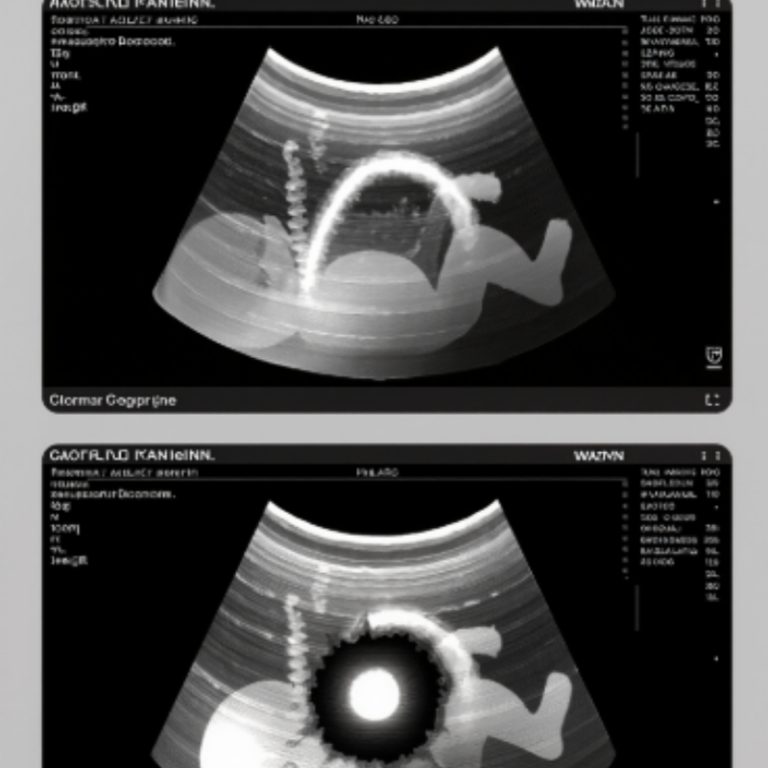

The second scan was done on a newer machine, one that looked like a cockpit. Again, the spine appeared, glowing beads along a dark riverbank. The gap remained, but this time it seemed to shift, as though unsure whether to stay open or close. The doctor adjusted angles, changed settings, then said quietly, “There’s some interference. It might be an acoustic shadow, but we have to prepare for both.”

During that final scan, the sonographer frowned, adjusted, and tried again. “I need to change the angle,” she said softly. She repositioned our baby with care and traced along his side. Slowly, the image sharpened. The white beads of the spine aligned perfectly—no break, no gap. Where darkness had once lived, light now ran unbroken. The room fell silent until she whispered, in disbelief, “It’s not a lesion. It’s an artifact—just an acoustic shadow.”

The surgeon leaned closer. “The shadow was caused by your old scoliosis hardware,” she explained. “Every scan angle caught it the same way.” Relief came not as a flood but a slow tide, pulling fear back out to sea. David bent over our baby’s blanket and said, “You little trickster. You comet of light.”